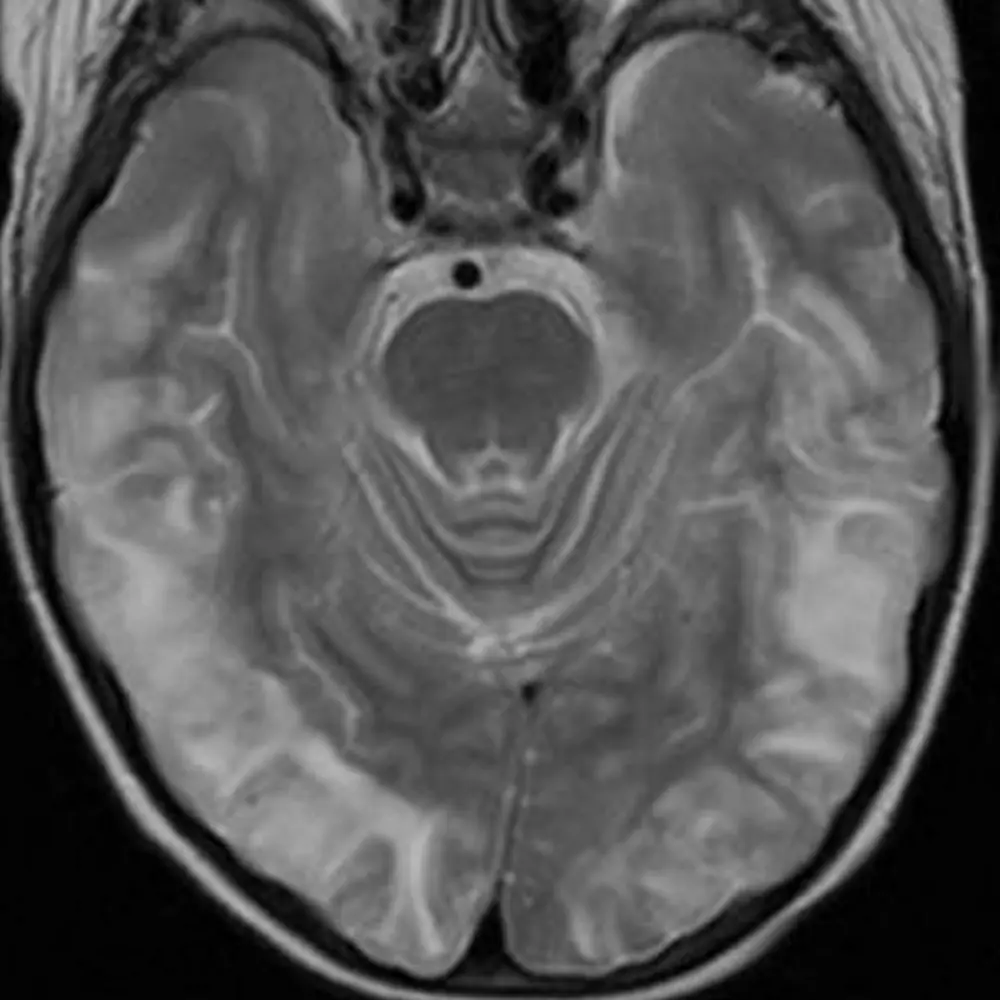

There are four deep cerebellar nuclei that are responsible for all of the signals leaving the cerebellum. The largest, most lateral, and only one that is easily identifiable on routine brain imaging is the dentate nucleus.

Most fibers from the deep cerebellar nuclei go through the superior cerebellar peduncle, cross in the midbrain (decussation of the superior cerebellar peduncles), and synapse on neurons in the ventral lateral (VL) nucleus of the thalamus. Some fibers from the dentate, emboliform, and globose nuclei go to the red nucleus. The fastigial nucleus also sends fibers to the tectum.

Dentate nucleus: motor planning, fine motor movements, cognition.

Interposed nuclei (emboliform + globose): limb movements and stability.

Fastigial nucleus: truncal movements, vestibular functions.